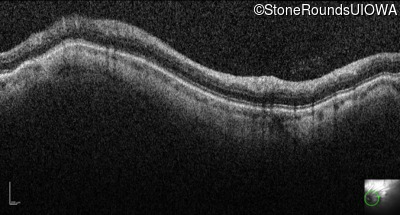

Infrared Fundus Photograph - Left - 20/100

Exemplar